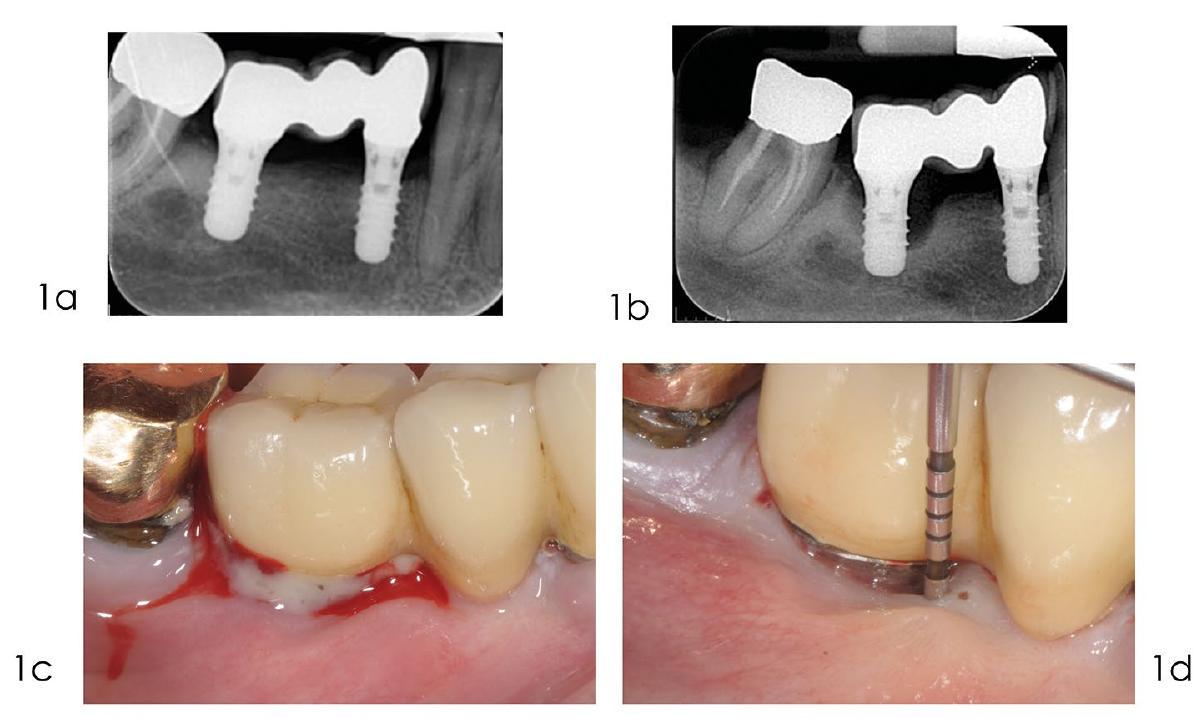

التهاب اللثة، وهو مرض التهابي مزمن تسببه البكتيريا، يتميز بتراكم أنواع الأكسجين التفاعلية (ROS) في مناطق محددة، مما يؤدي إلى استجابة التهابية، والتي بدورها تؤدي إلى تدمير الأنسجة الداعمة للثة. لذلك، فإن استخدام مضادات البكتيريا، والتخلص من ROS، وتقليل الاستجابة الالتهابية، وتنظيم البيئة الدقيقة للثة، وتخفيف امتصاص العظم السنخي هي طرق فعالة لعلاج التهاب اللثة.…